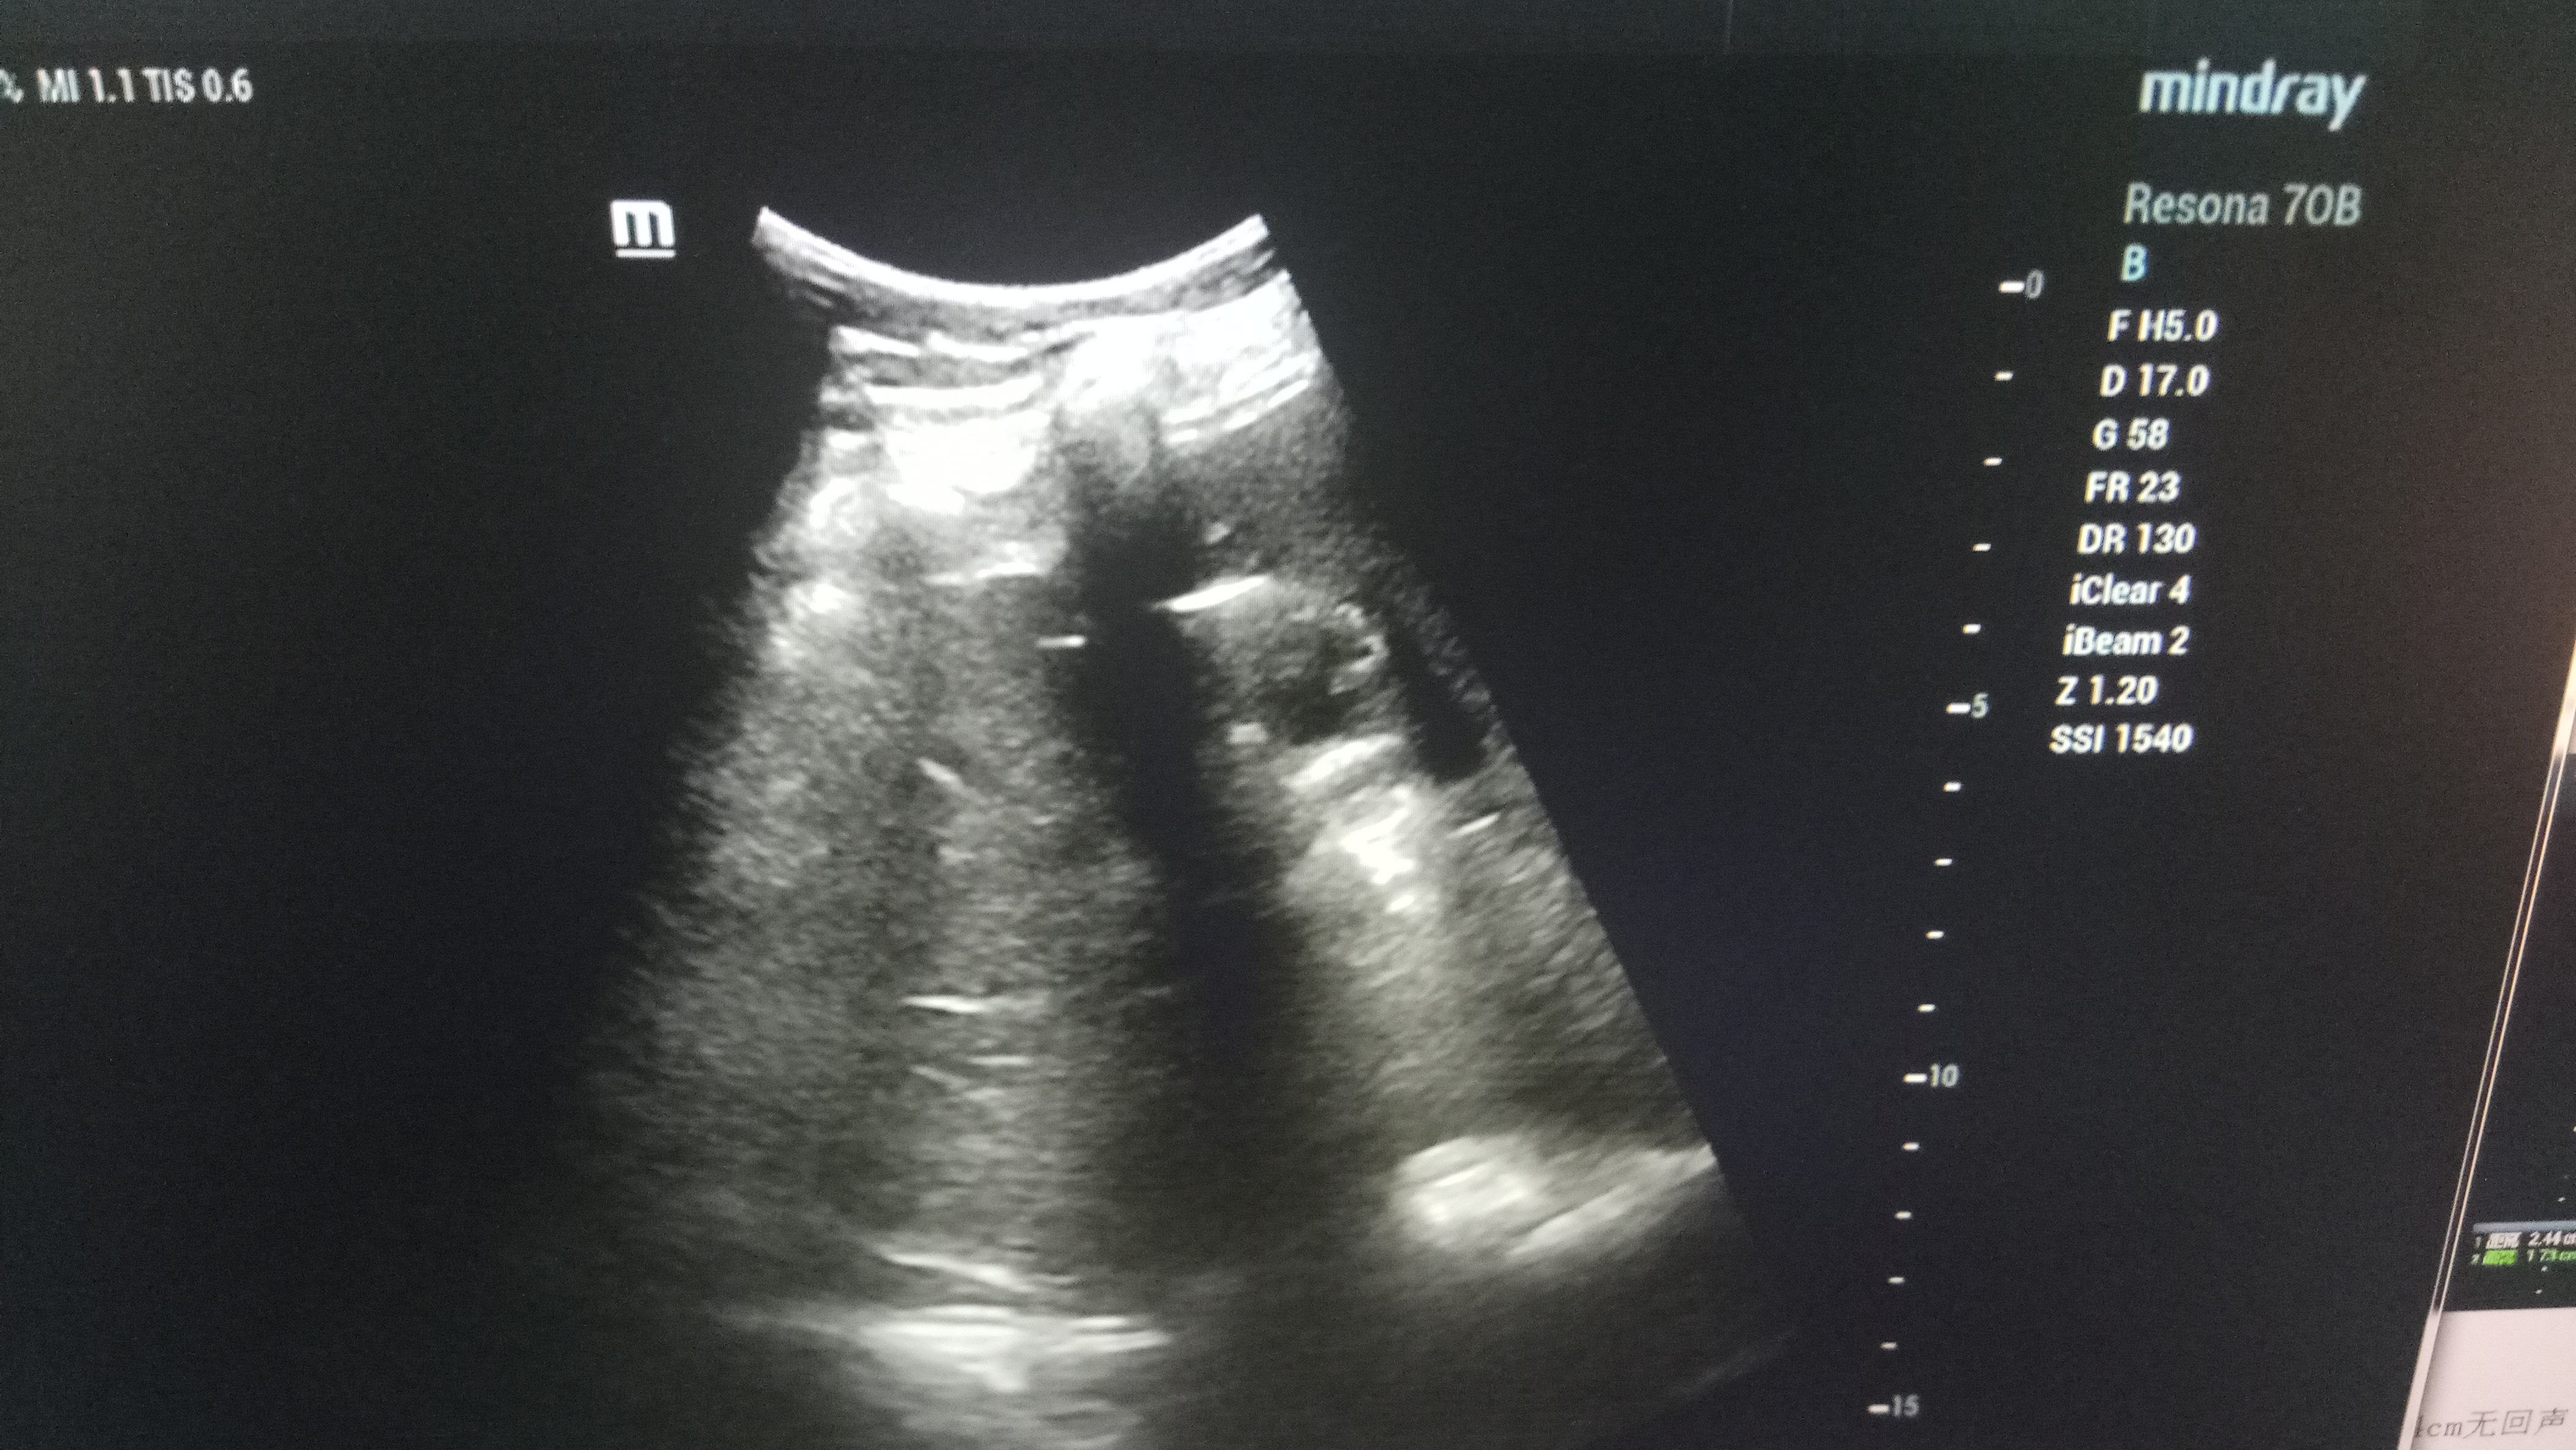

近日,啄木鸟 超声科在高陵区医院成功开展了一例超声引导下肝囊肿抽吸硬化治疗术。患者前段时间查出肝囊肿,因开腹手术风险性大且痛苦,遂联系了高陵区医院超声科,在啄木鸟 超声科主任展小军与对口支援医生杨艳秋的紧密配合下,短短30分钟,通过一根穿刺针,直径近7cm的肝囊肿就被完全抽吸硬化完毕,患者生命体征平稳,休息几小时后已活动自如。

超声介入微创诊疗技术是在实时超声的监视和引导下,完成各种穿刺、活检以及抽吸、插管、注药治疗等操作,达到与外科手术相当的效果,具有创伤小、恢复快、无辐射、介入治疗定位精确等优点。可治疗全身各部位囊肿,尤其是巧克力囊肿效果更佳,还有全身各部位肿瘤的活检和治疗,超声引导下微创治疗是未来医学发展方向。